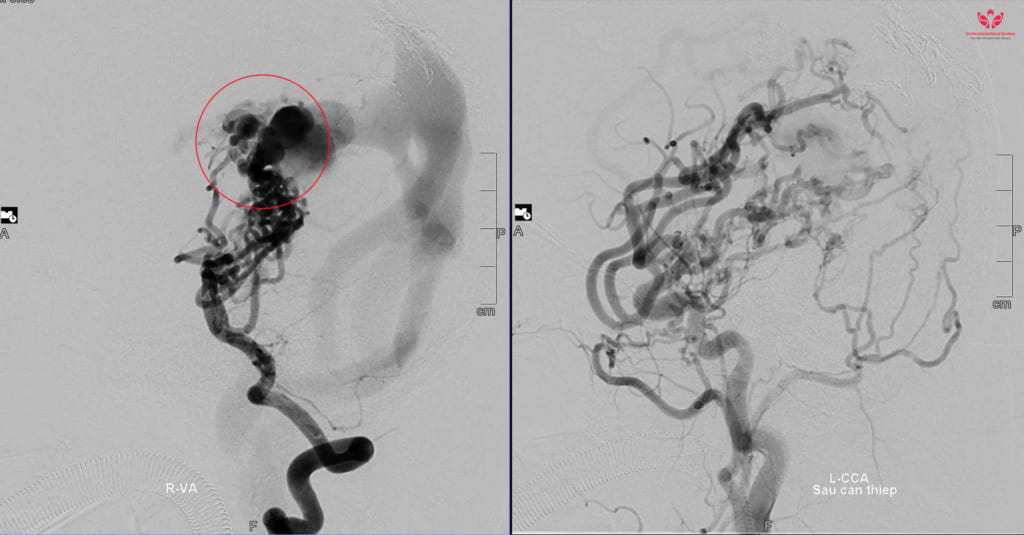

Ngay khi chào đời tại Bệnh viện Nhi Đà Nẵng, bé N.P.T.D đã rơi vào tình trạng tím tái, suy tim cấp, suy hô hấp nặng. Các bác sĩ phát hiện trong não bé có khối dị dạng mạch máu não bẩm sinh, có nhiều động mạch nuôi phức tạp và lưu lượng máu chảy qua rất cao.

Các chuyên gia đầu ngành trong và ngoài nước đã hội chẩn, đều nhận định đây là trường hợp dị dạng mạch máu não khá lớn và phức tạp, rất khó để can thiệp.

Khi bé D. vừa tròn 1 tuổi, TS.BS Trần Chí Cường đã có ca can thiệp đầu tiên cho bé tại Đà Nẵng. Các bác sĩ trong ekip can thiệp cho biết: Lần can thiệp này là một thử thách lớn, trong khi khối dị dạng phức tạp thì bệnh nhi lại còn quá nhỏ, dụng cụ can thiệp hạn chế.

Sau nhiều nỗ lực, lần can thiệp đầu tiên đã thành công, vượt ngoài sự mong đợi. Chiến lược can thiệp được các bác sĩ hội chẩn là can thiệp nhiều lần cho bé để giảm nhẹ, giảm nguy cơ vỡ khối dị dạng. BS.CKI Dương Hoàng Linh, đơn vị can thiệp DSA, bệnh viện S.I.S Cần Thơ chia sẻ thêm:

Suốt 10 năm, bé D. đã trải qua 8 lần can thiệp mạch não. Mỗi lần là một cuộc chiến sinh tử, đòi hỏi bản lĩnh và sự tận tâm của đội ngũ y bác sĩ cùng niềm tin mãnh liệt từ gia đình.